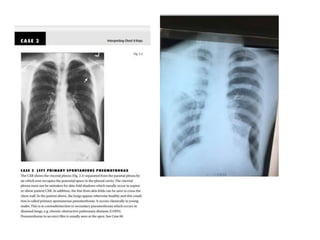

pathologies

Silhaete sign

Silhoutte can be applied to collapse